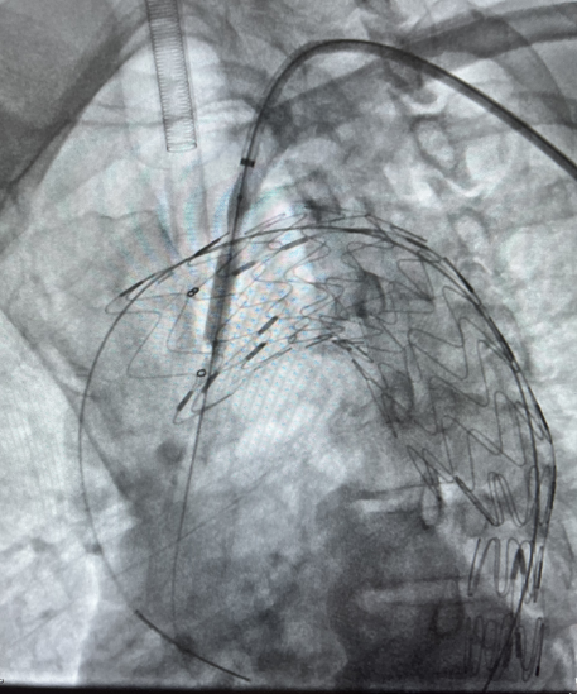

case 3

III型弓合并长段动脉瘤病变,LSA开口位于瘤体且与主动脉弓夹角小,病变累及长度长,手术截瘫风险高。

传统开窗技术因血管成角小、路径迂曲难以精准定位。

通过三开窗技术(LSA+LCCA+其他分支)完成重建,Futhrough系统的高顺应性和行程控制能力有效避免了血管损伤,术后截瘫风险显著降低。